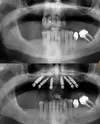

Implant tedavisi